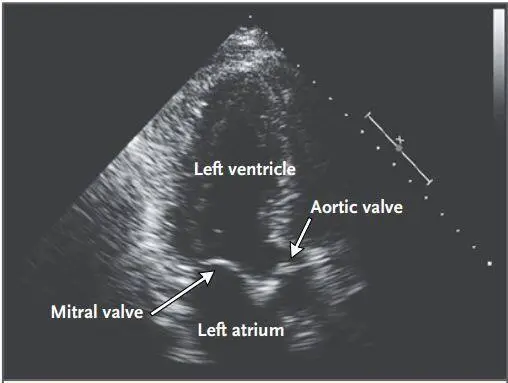

2 周后随访,患者出现收缩期杂音。心脏超声可见左心房二尖瓣表面一长约 7 mm,宽 6 mm 的赘生物,伴轻度主动脉瓣狭窄和中度主动脉瓣功能不全。无法测量收缩期肺动脉压(图 3)。患者无发热,无心脏症状,无心内栓塞的表现。三次血培养均为 (-)。

图 3. 经食管心脏超声。主动脉瓣非冠状尖端可见一活动的赘生物。

心内科医生认为赘生物很可能是惠普氏病的并发症,建议继续使用抗生素治疗。抗生素治疗 2 个月后,患者自述咳嗽、外周水肿、关节痛、肌痛和疲劳感缓解。治疗 6 个月后, 心脏超声提示心脏赘生物消失,但仍有瓣膜关闭不全(图 4)。